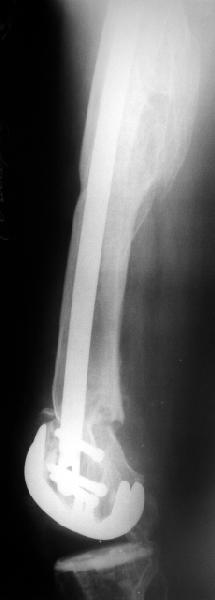

В итоге сделали антеградный остеосинтез. В дистракторе свежий перелом вправился сразу, а вот старый - оставил проблему, дистальный отлмомк остался все равно кзади. И гвоздь бы прошел кпереди от него, а ретроградный - перфорировал бы передний кортекс. Так что пришлось еще сделать чрескожную остеотомию через перелом, чтобы малость мобилизовать дистальный отломок. Снимки в прилжении.

The radiographs look excellent and a good outcome would be anticipated. The idea to osteotomize the femur shaft to compensate for the prior shaft malunion was clever and should work fine.

I can't actually see the osteotomy on either radiograph. Is it more proximal than we see in these radiographs or so well aligned as to be not visible?

The osteotomy was perfromed trough the fracture site. See the image.